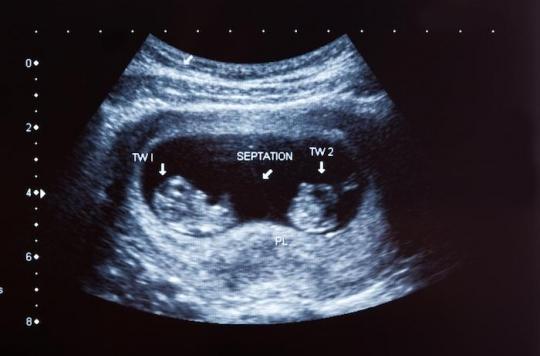

Kyste ovaire bébé échographie forum-Bonjour Docteur, j'ai fait aujourd'hui ma deuxième échographie tout va bien sauf que mon bébé a deux kystes au cerveau Le médecin m'a dit de ne pas m'inquiéter car normalement ils Enfaite ma femme âgé de 27 ans est enceinte 16eme semaine et l'hors de notre dernier échographie le docteur nous a informé que le bébé dispose de deux kystes au niveau du cerveau malgré que ça croissance est normale et ces organes aussi ainsi que le test trisomie 21 est négatif Le docteur nous a conseillé de faire le test amniocentèse